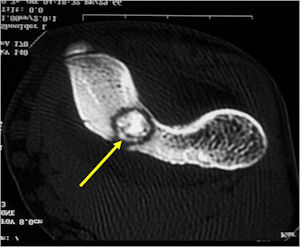

CT Scan:

- Well defined nidus with a smooth peripheral margin; +/- mineralization (CT more sensitive than XR and MRI for detecting mineralization); CT is better for detecting nidus in presence of exuberant sclerosis

- CT is more useful for detecting the nidus if there is extensive edema